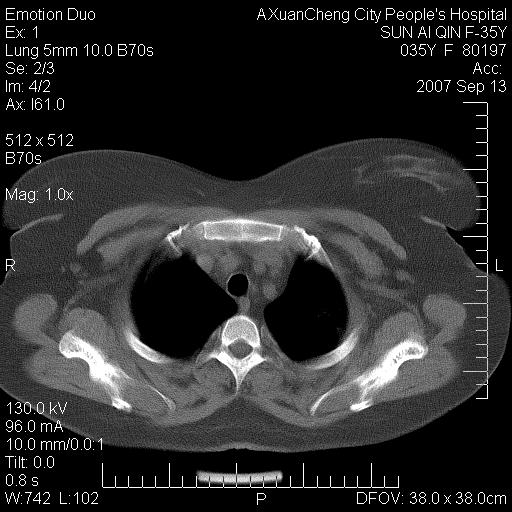

以下是引用天南地北在2007-9-13 13:43:00的发言:[br]考虑双肺、肺门侵润

以下是引用ydx_74在2007-9-13 15:42:00的发言:[br]仅看片,考虑右上肺癌并双肺转移,结合病史,考虑肺门、肺内淋巴侵润

以下是引用同在2007-9-13 15:08:00的发言:[br]支持肺门及双肺侵润.